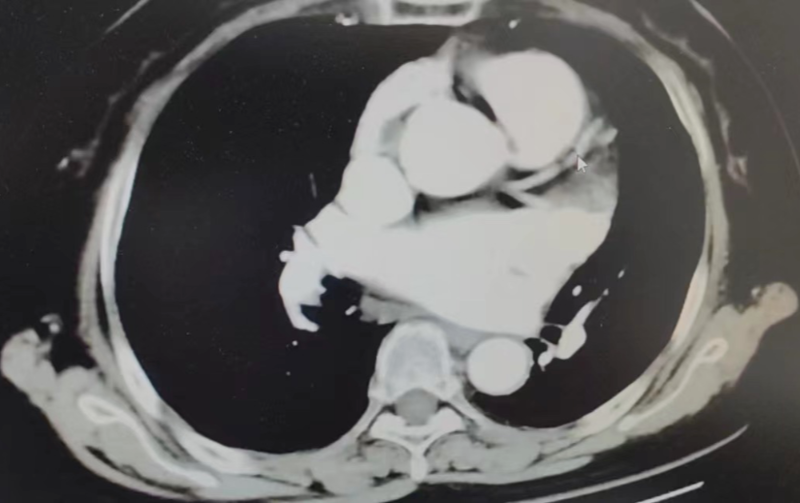

经过完善的术前CT和全面的Truplan软件术前分析准备。在介入室的全面配合下完成该患者的术前准备工作,谢桂庭进行房间隔穿刺,精准定位穿刺位点。行左心耳造影,造影结果显示开口28mm左右,深度32mm左右。结合术前Truplan结果以及术中DSA测量结果,选用WATCHMAN 33mm封堵器进行封堵。